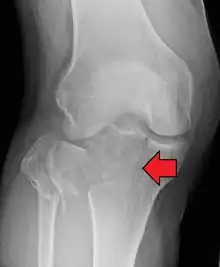

Subtle tibial plateau fracture on an AP X ray of the knee

A tibial plateau fracture seen on X-ray